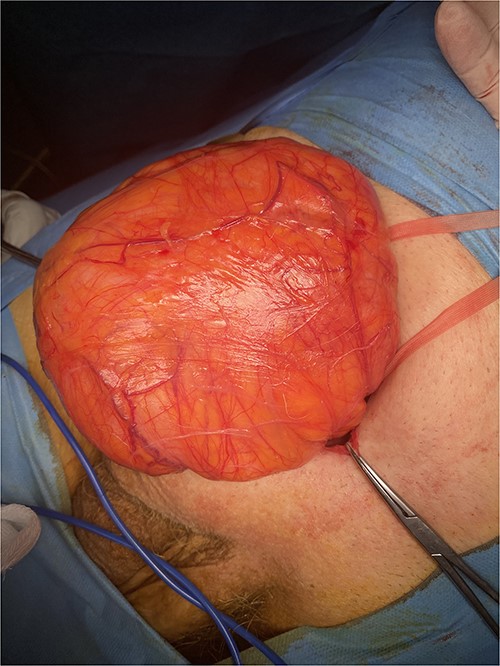

Following multidisciplinary consultation, a stent placement was considered too dangerous for ureteral injury because of acute angulation. Therefore, a primary repair of the inguinal hernia was decided. Because of the patient’s comorbidities, an open approach was favored. Intraoperative dissection revealed an indirect hernia with protrusion of a peritoneal sac containing small bowel loops and large amount of retroperitoneal fat (Fig. 2). The hernia sac containing the bowel loops and ureter was reduced without opening the sac to avoid iatrogenic injury of the ureter. The hernia was repaired with mesh placement according to the Lichtenstein technique (Fig. 3). The postoperative course was uneventful, with resolution of fever and gradual decrease of inflammatory markers. The patient was discharged safely on the fourth postoperative day, with complete resolution of hydronephrosis and normal renal function. Within a 6-month follow-up, no other complication was reported.

Intraoperative image showing the final reconstruction after mesh placement.